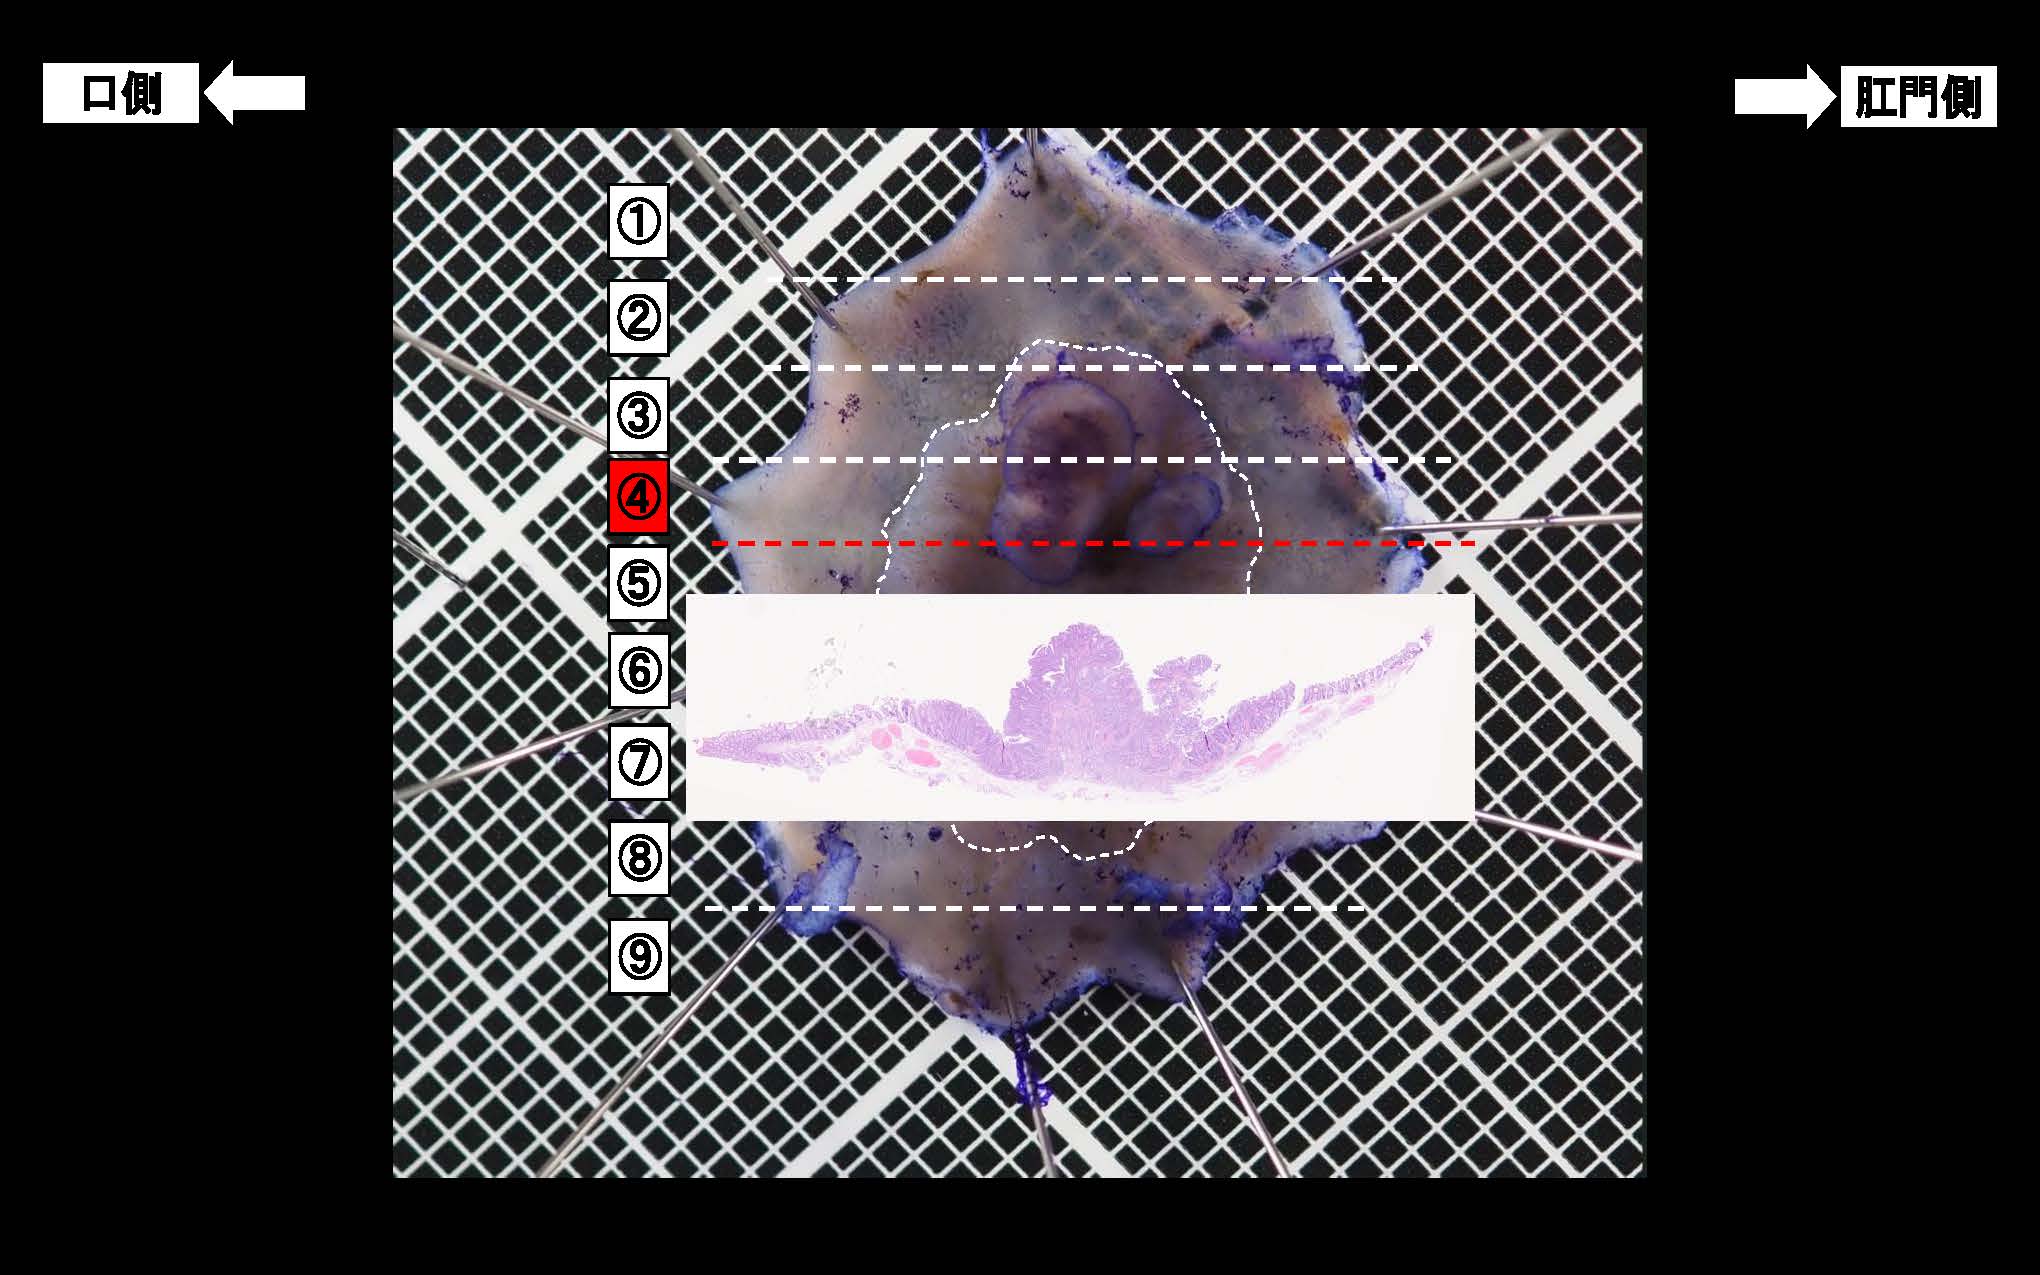

消化管Mapping~大腸~ 2025.6.11

消化管Mapping